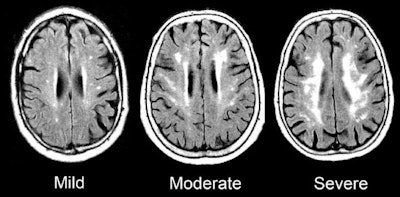

MRI scans were performed on the final visit to look for evidence of white-matter damage. The researchers also took blood samples at three visits to measure for high-sensitivity C-reactive protein, a standard indicator of inflammation. Subjects with at least 3 mg/L of C-reactive protein were considered to have elevated inflammation.

Overall, increasing and chronic inflammation were associated with the most damage to white matter; therefore, there is reason to infer a cause and effect relationship between growing and persistent inflammation and evidence of dementia, according to Walker. The researchers stopped short of saying their results were conclusive, however.